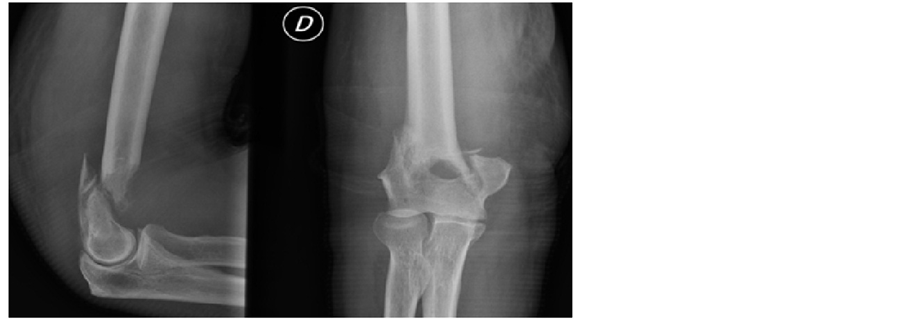

Our patient underwent radiographic assessment is an x-ray of the right elbow and face profile

Our patient underwent radiographic assessment is an x-ray radiography face and right elbow profile (Figure 1) with an elbow CT (Figure 2) which has objectified a supra-condylar humerus fracture on a lytic lesion.

Figure 1. X-ray radiography face and right elbow profile.